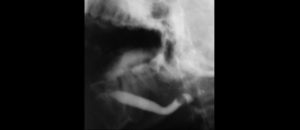

La Condromatosis Sinovial (CS) es un proceso metaplásico en el que la sinovial de una articulación produce y finalmente secreta cuerpos cartilaginosos en el espacio